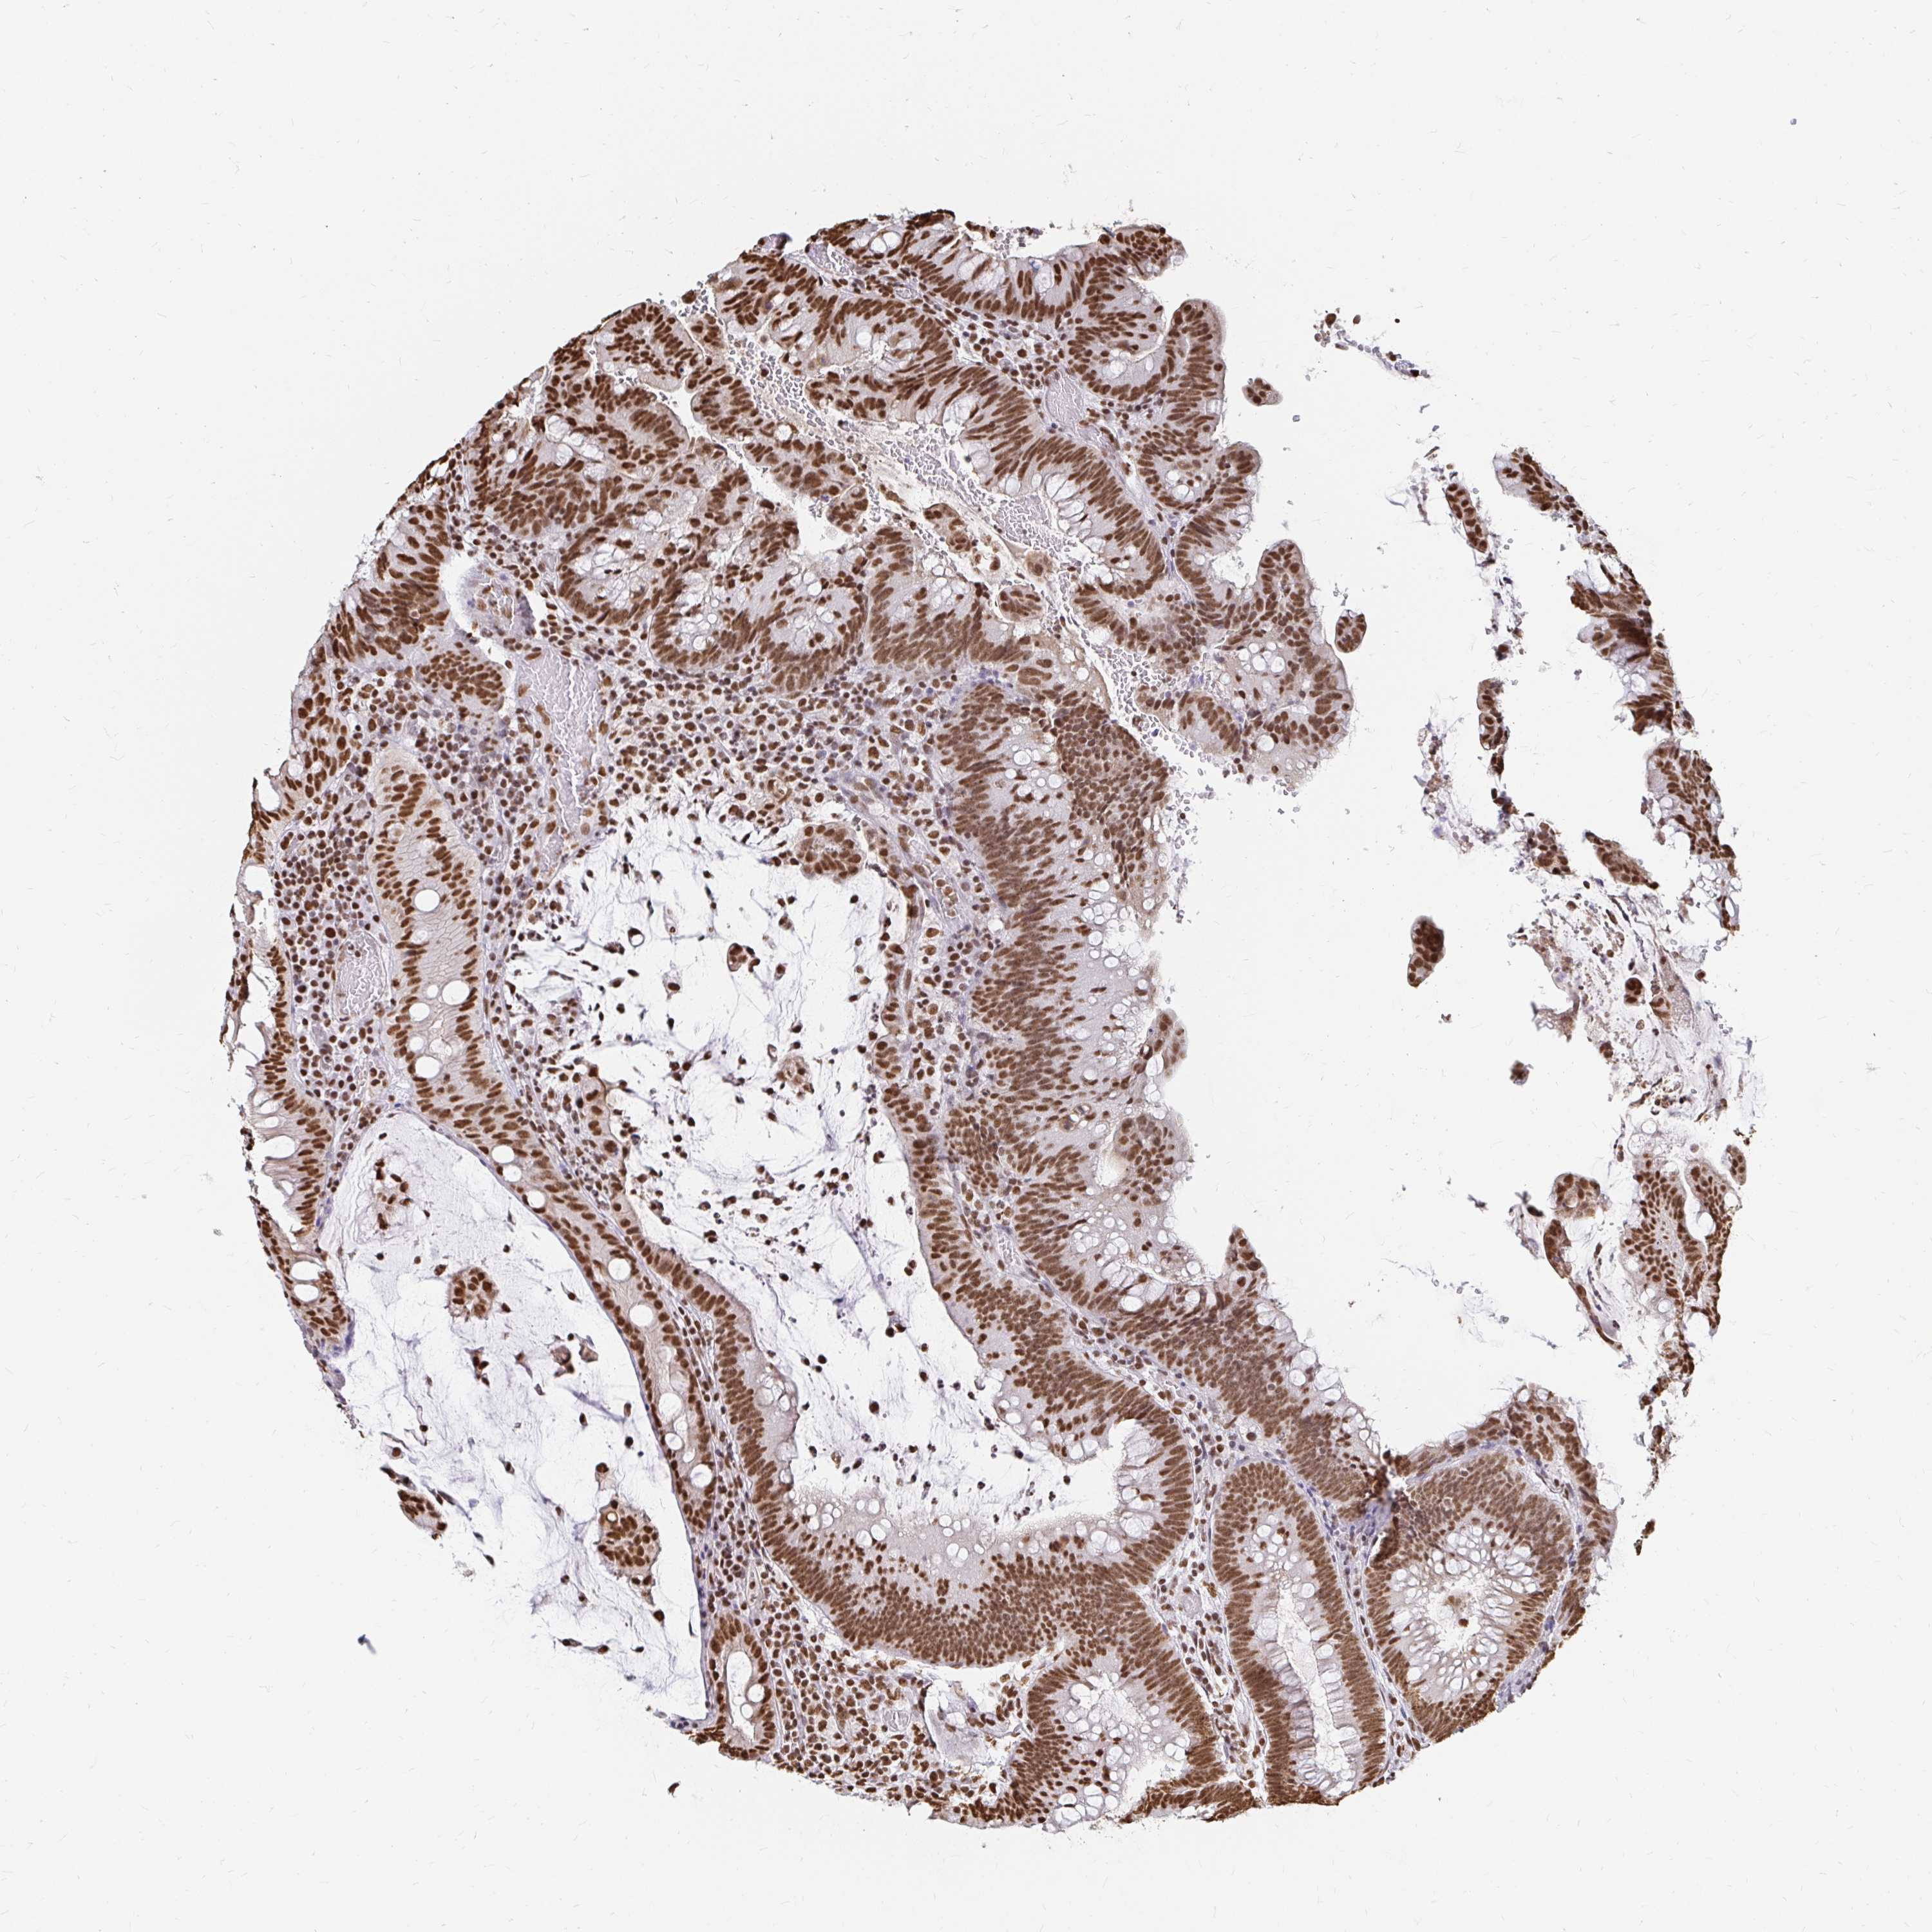

HNRNPU

CANCER COLORECTAL CANCER Show tissue menu

Colorectal cancer

Human cancer

Rectum adenocarcinoma